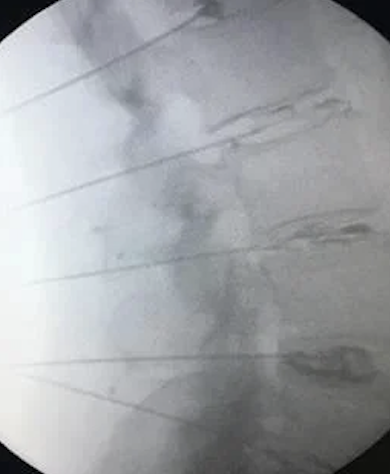

During your annulogram™, we inject X-ray contrast and a trace of antibiotic into each disc's outer annulus fibrosus to reveal tears. Then, The medication is promptly injected to seal the tears and promote tissue growth, healing the discs over time.

During the Discseel® Procedure, lasting about 40 minutes in an outpatient setting, you'll receive mild sedation for comfort. Using x-ray fluoroscopy, your physician will inject contrast mixed with an antibiotic into each disc, pinpointing disc tears. Then, under x-ray guidance, essential components of Fibrin are injected into the tears, sealing damaged discs. Over months, Fibrin promotes tissue growth, aiding in disc healing.